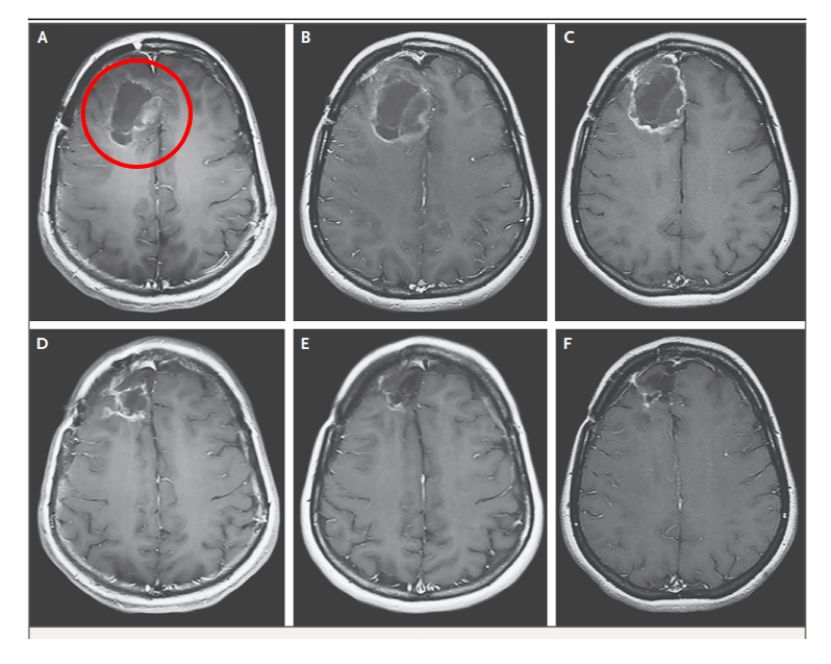

大家可以明显看出,治疗前,患者肿瘤已复发,有一个非常明显的脑瘤(图A),使用溶瘤病毒后,肿瘤慢慢地缩小,而且随着时间推移,效果越来越好,肿瘤没有复发迹象。5年以后再次做大脑扫描,发现肿瘤已经完全消失了(图F)!